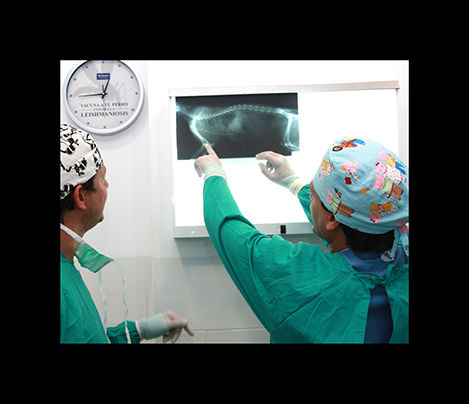

radiología

La radiologia es imprescindible en traumatologia y en algunos diagnosticos, ya sea mediante radiologia simple ó de contraste.

traumatología

En clinican podemos tratar las diversas afecciones que pudan afectar a huesos y articulaciones